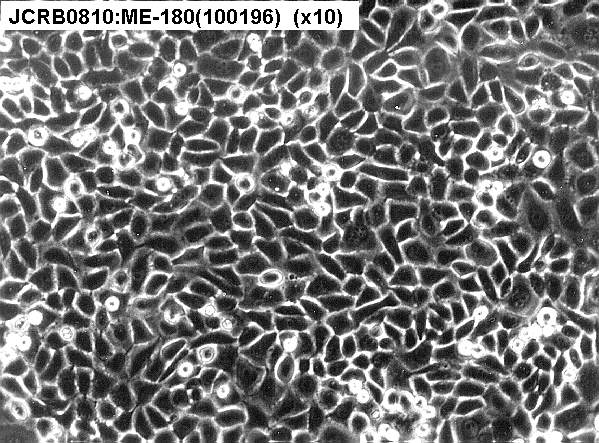

ME-180细胞ATCC HTB-33人子宫颈表皮癌细胞特点和简介

这株细胞来源于一个细胞集落不规则没有显著角质化的侵染性鳞状细胞癌。 单层培养的细胞间可以观察到带状连接,也注意到有细胞质张力丝。 1970年发现支原体污染并去除。 肿瘤坏死因子(TNF)α抑制ME-180细胞ATCC HTB-33的生长。 这株细胞含有人乳头瘤病毒(HPV)DNA,与HPV-39的同源性高于HPV-18。 在本库通过支原体检测。 在本库通过STR检测。